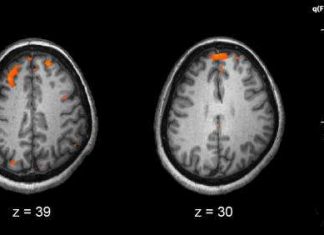

Study: Anabolic androgenic steroids accelerate brain aging